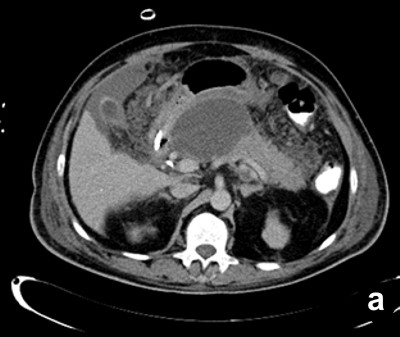

Twenty-four patients (48.0%) underwent image-guided drainage of the pancreatic/peripancreatic collections. Nine of these patients (37.5%) were successfully managed by radiological intervention only (Figure 2) while 15 (62.50%) continued to have or developed infection, persistent organ failure or locoregional complications. These 15 patients were subsequently operated upon (Figure 3). There were a total of 11 procedure-related complications in these patients (73.3%) with two patients having catheter slippage which required repositioning (Table 1).

Figure 3. a. Well-defined collection within the pancreas in a patient with gallstone-induced pancreatitis on the 21st day (nasojejunal tube is seen in the duodenum). b. Percutaneous catheter inserted the next day. c. Sixteen days later, the collection showed regression but the inflammation persisted. The patient had deteriorated and was operated on. |